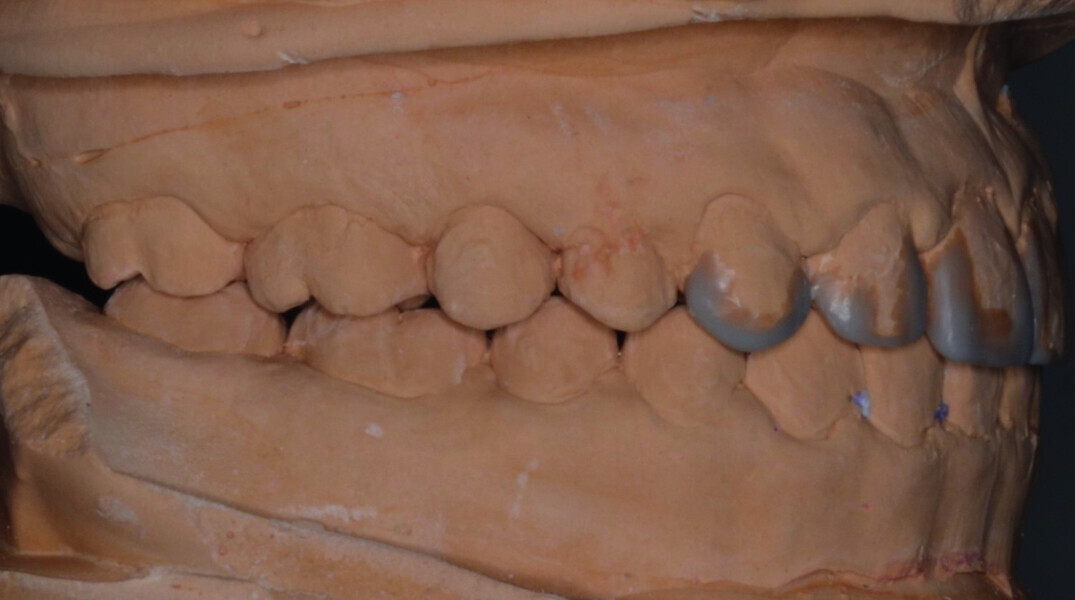

Orthodontic management of maxillary lateral incisors agenesis